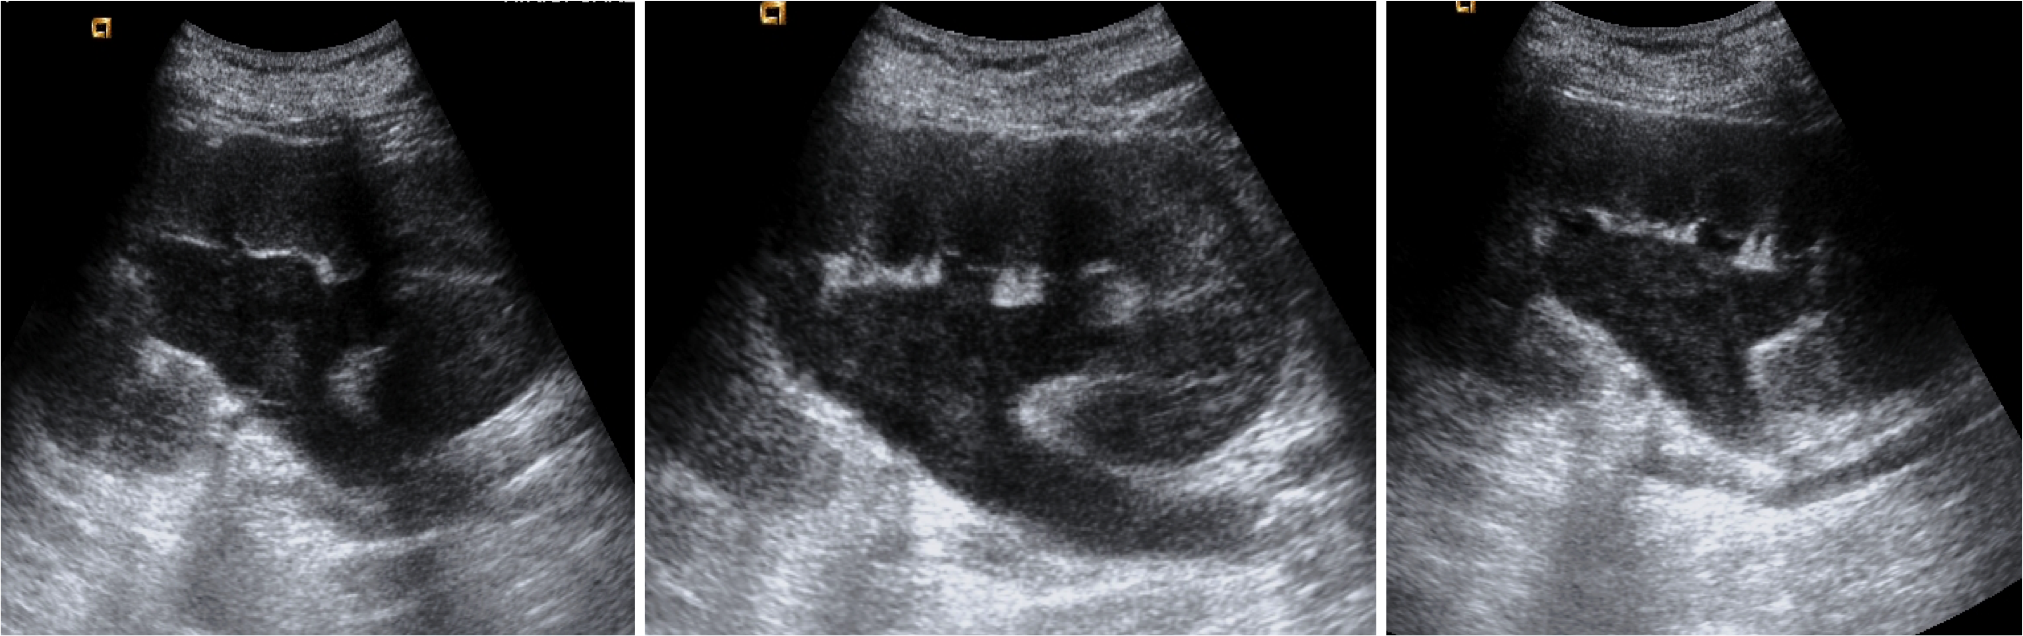

Ecografía:

- Debris ecogénicos en el interior del sistema colector: es es signos más fiable para diagnosticar una pionefrosis (S 90%, E 97%).

- Dilatación del sistema pielocalicial.

- Niveles líquido-líquido en el sistema colector.

- A veces pueden verse ecos sucios correspondientes a gas.

- Engrosamiento de la pared de la pelvis (>2mm).